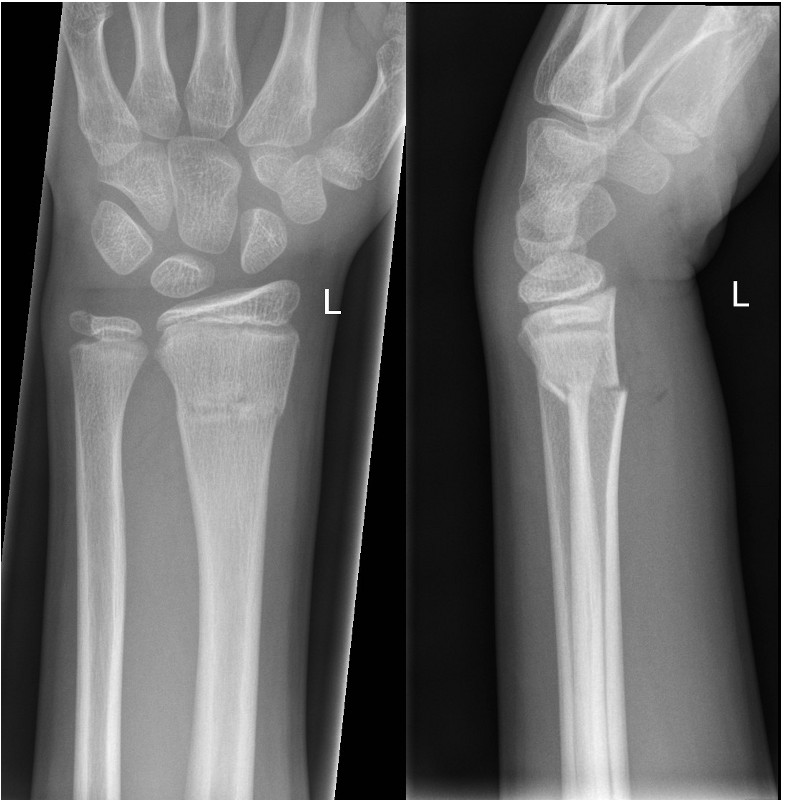

Left image: Transverse fracture of distal radius with 15 degree dorsal angulation

Right image: Completely displaced fracture of distal radius and ulna